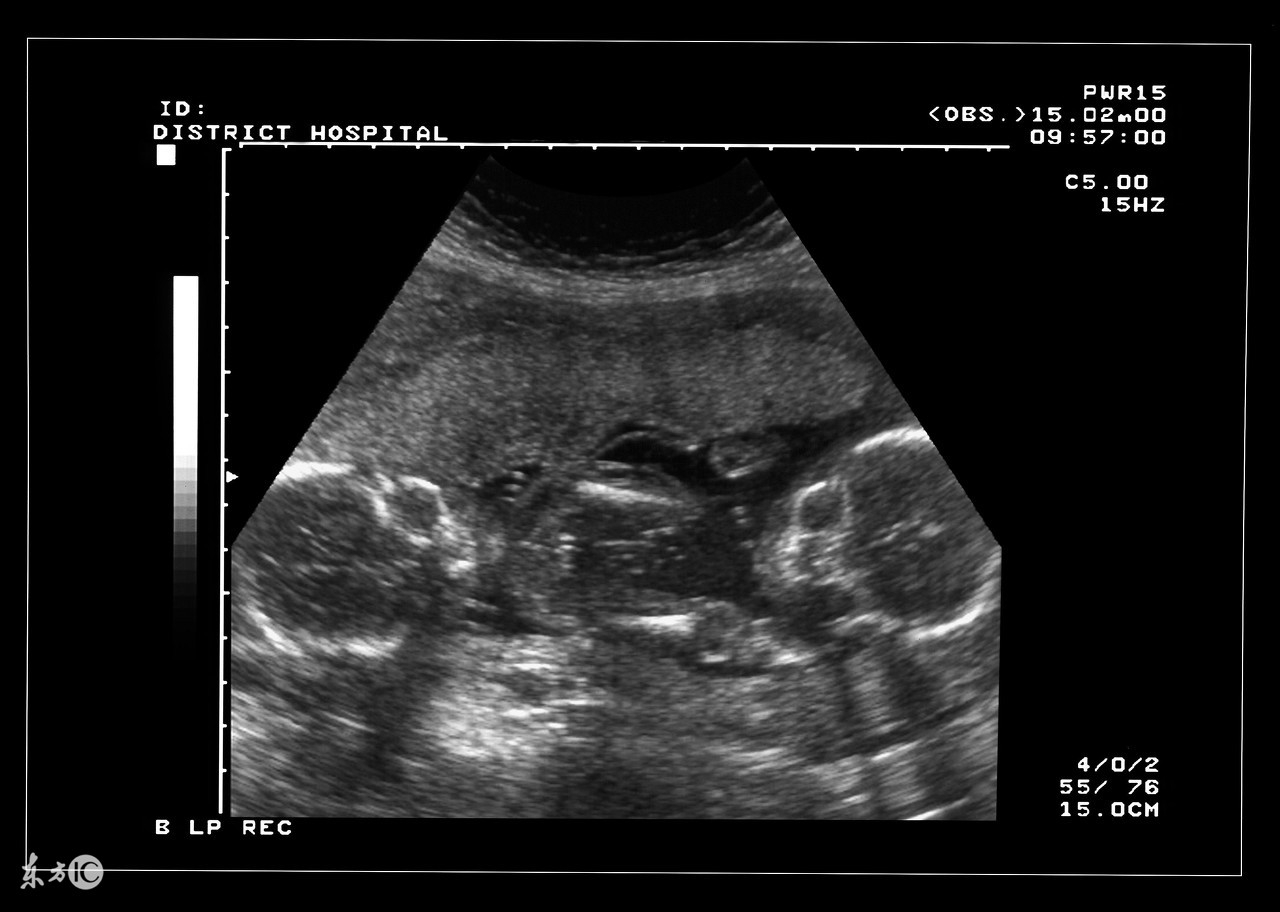

双胞胎确实是一件可想而不可求的事情,当孕妇怀上双胞胎或者多胎后,使母体长期处于超负荷的状态,在预产期到来之前,准妈妈需要就是否实施剖腹产的问题预先与家人和医生达成一致,并为此做好准备。大家都知道,自然分娩是最理想不过的,但实际上为了确保安全,大部分多胞胎最终实施的都是剖腹产。

双胎妊娠检查非常重要。由于双胎孕妇比一般孕妇子宫明显增大,这不仅增加了孕妇身体的负担,还由于对其心、肺及下腔静脉的压迫而容易产生心慌、呼吸困难及下肢浮肿等不适。双胎妊娠出现妊娠合并症者也较多,其妊高娠的发生率明显高于一胎妊娠,所以双胎妊娠者要听从医嘱,按期去医院接受检查。

双胎妊娠由于子宫腔相对狭窄胎盘血液循环障碍,其流产发生率较单胎妊娠高2—3倍,因此应加强孕期保护与监护。若一胎发生死胎,另一胎仍可继续生长发育,死亡的胎儿将被吸收或挤压成纸样儿随正常胎儿娩出,不必担心害怕,更不要引产终止妊娠。因双胎妊娠子宫过度膨胀,易发生早产,故应于中期妊娠后注意休息,避免房事,并提前4周做好分娩前的准备工作。由于妊娠的并发症尤其是妊高娠的发生率比较高,从母子安全斟酌,应在预产期即住院待产,以免发生早产或其他不测。